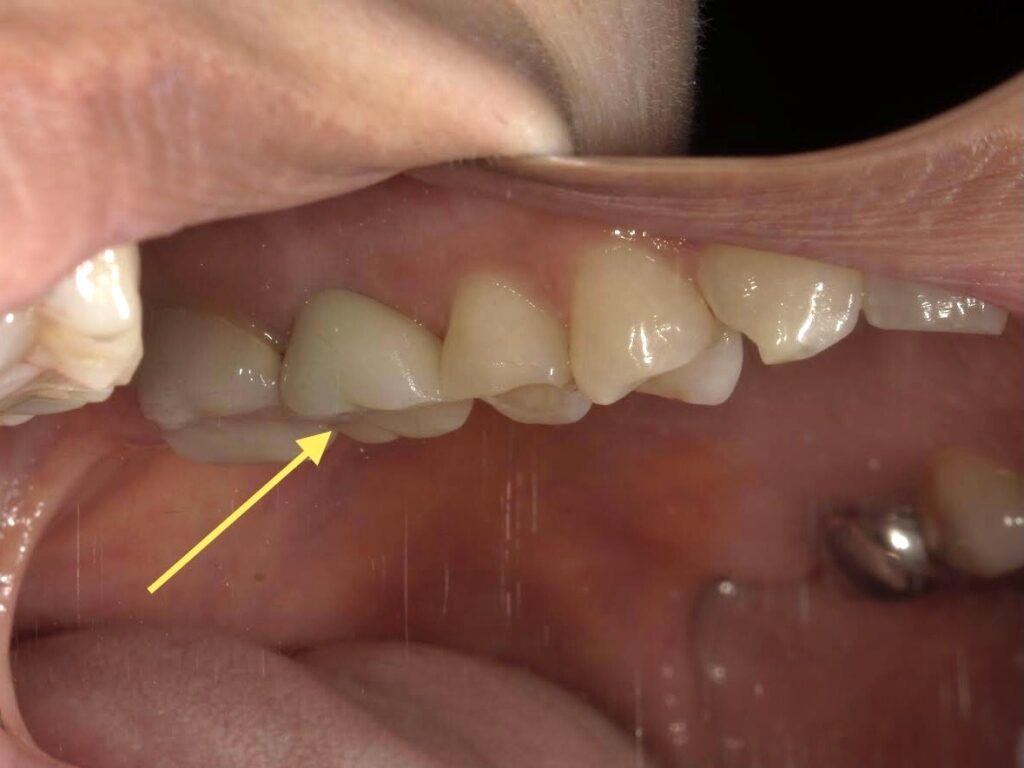

【A様】

側方面観(開口)

年齢 | 30代後半 |

性別 | 女性 |

主訴 | 歯を抜いた後、周りの歯を削ることなく噛めるようにしたい |

施術内容 | 右上第一大臼歯欠損部にインプラントを埋入し、ジルコニアクラウンを被せてあります |

治療期間 | 約1年(抜歯からジルコニアクラウン装着まで) |